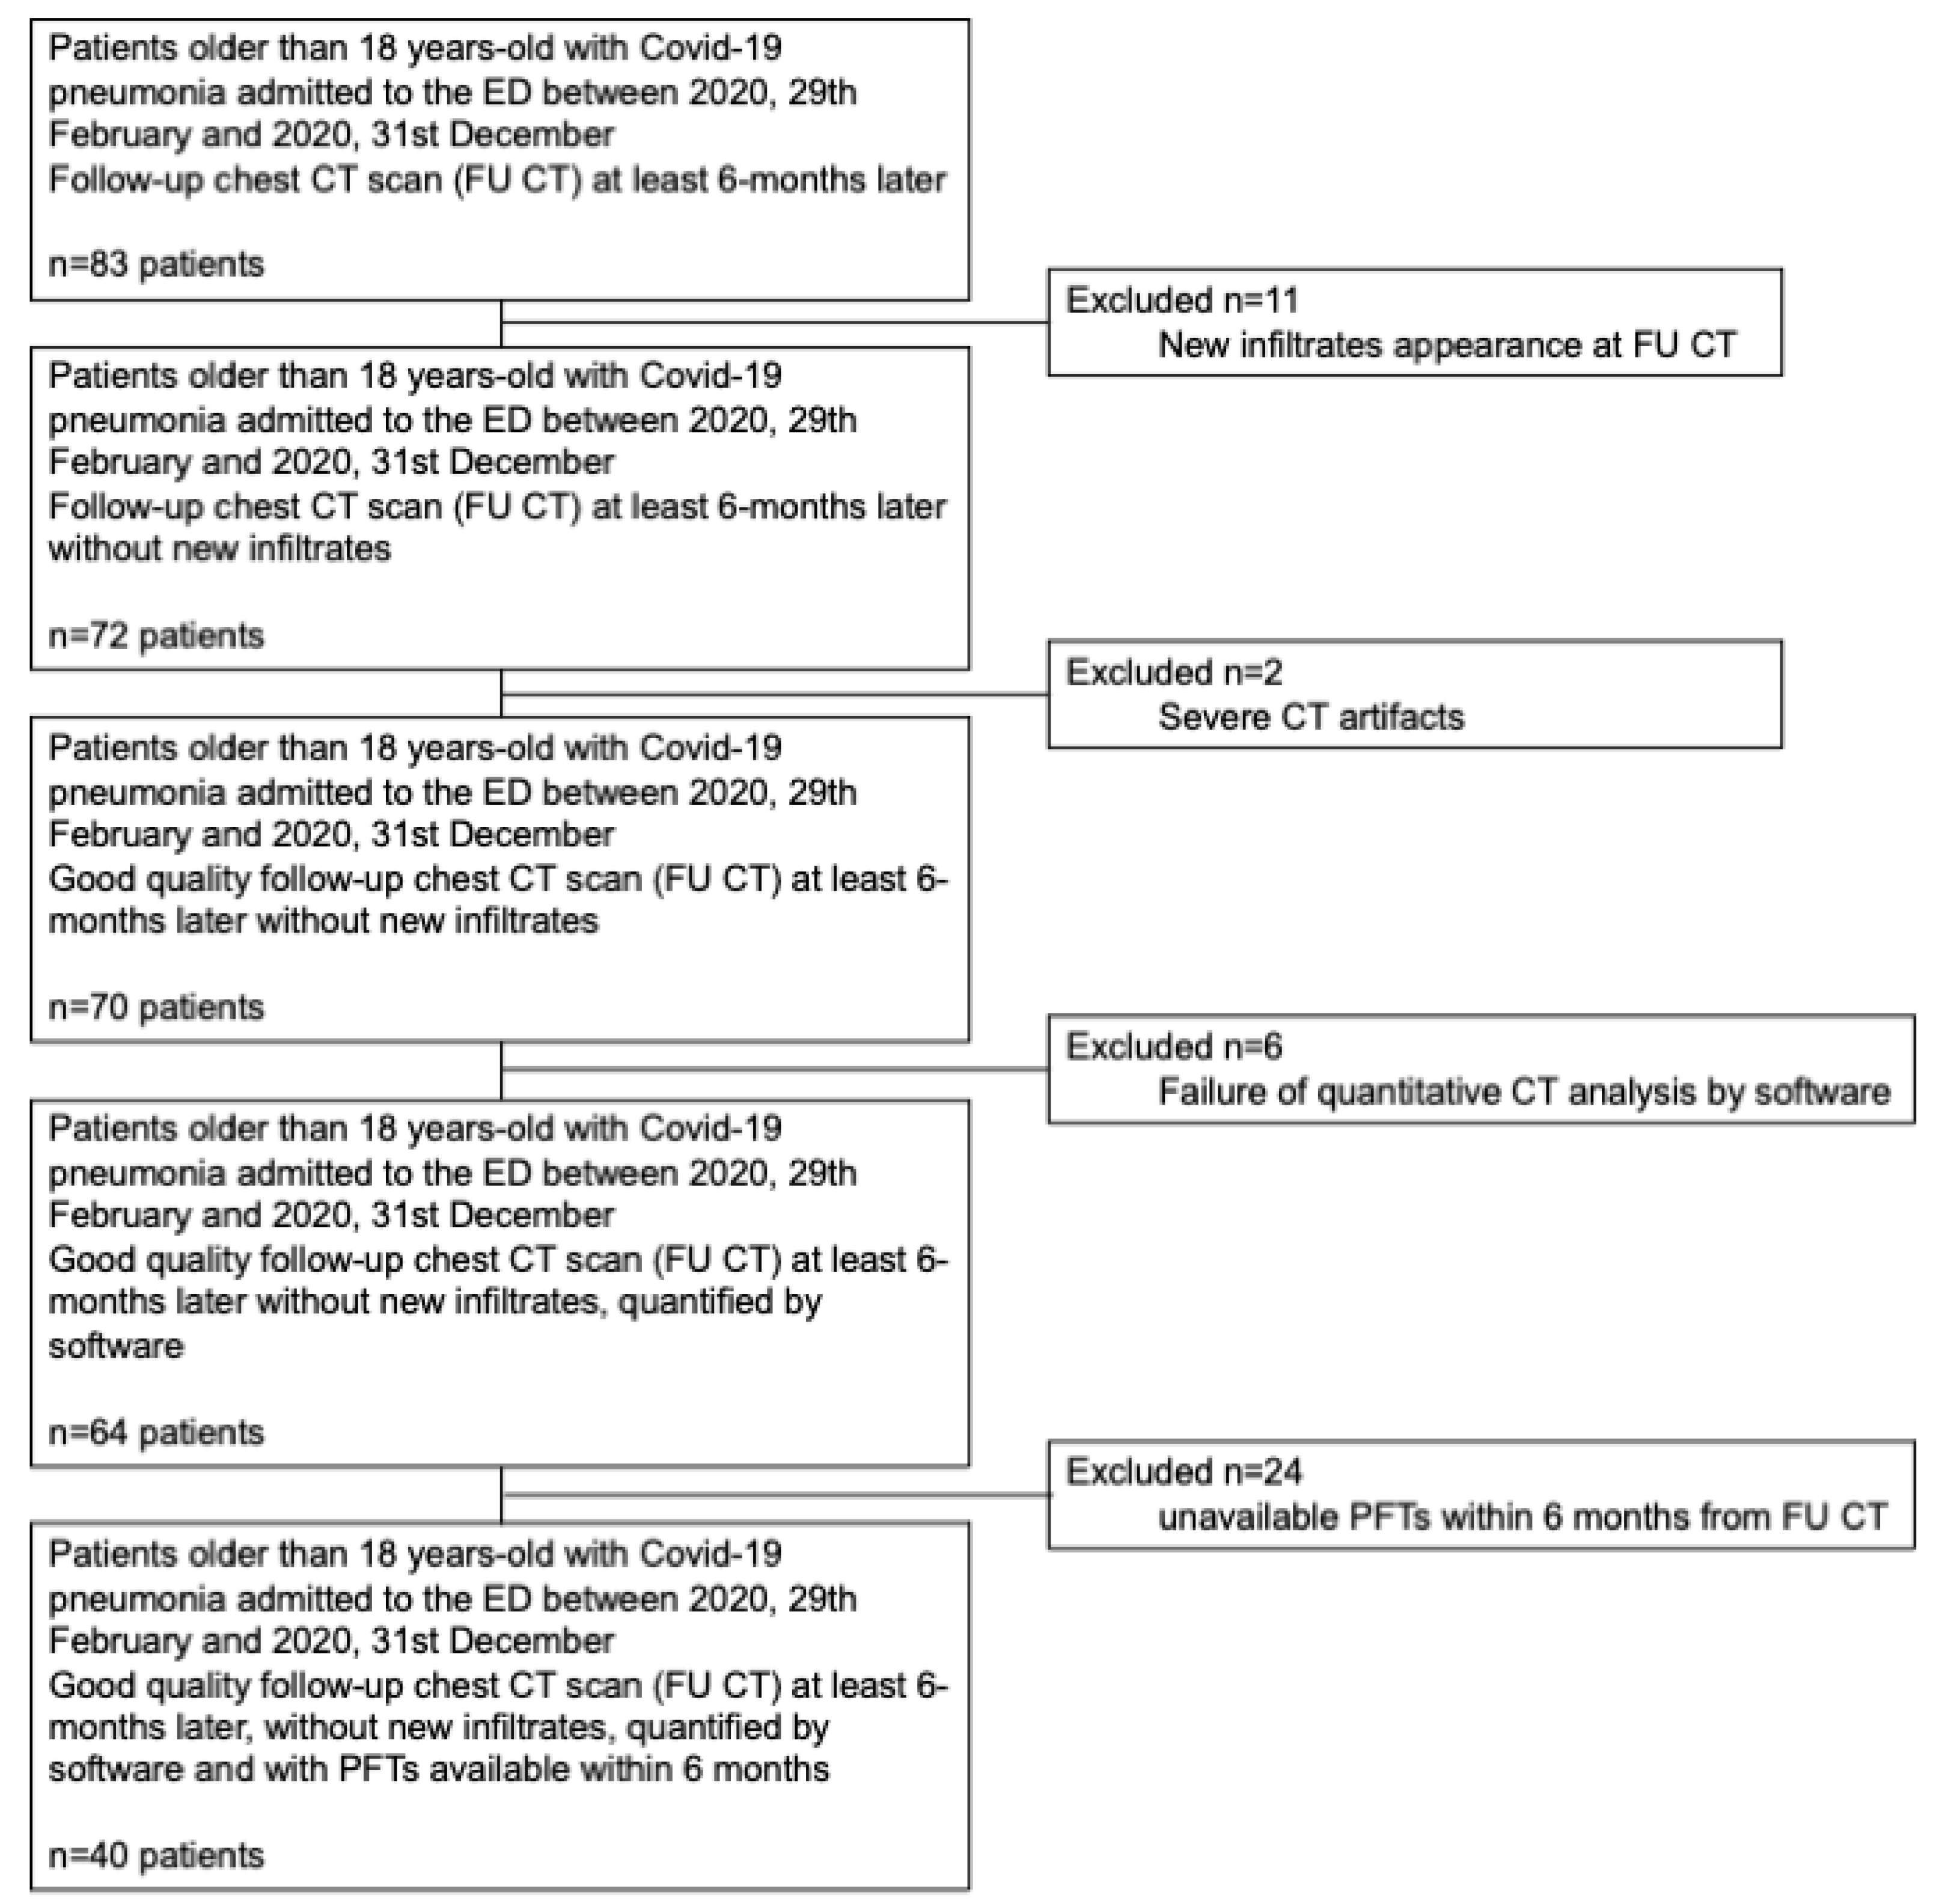

2.1. Study Population